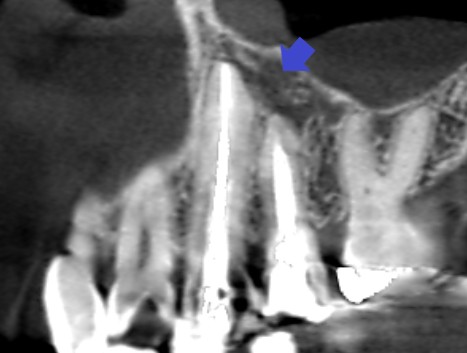

左上の犬歯と第一小臼歯のCT画像です。赤い矢印の先に、犬歯と第一小臼歯の両方の根の先にかかる大きな膿の影がみられます。